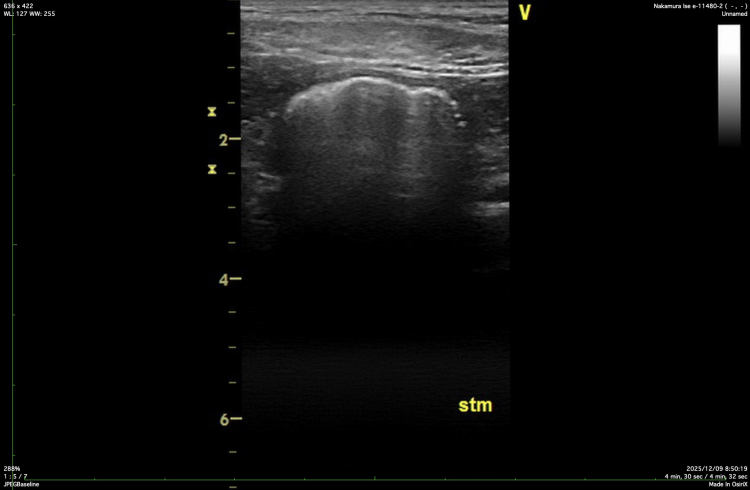

超音波(エコー)検査では、十二指腸の拡張を確認しました。

一方で、胃の中はガスが充満しており、内部構造を十分に評価することができませんでした。

胃のエコー画像